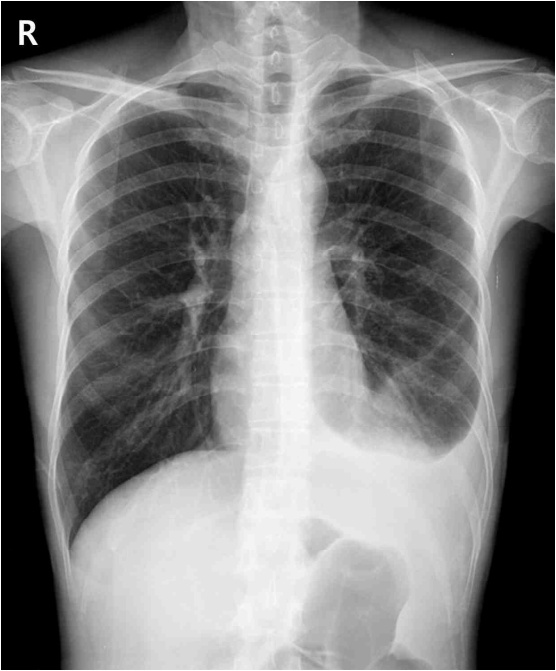

33세 남자가 1주 전부터 숨이 찬다며 병원에 왔다. 1개월 전부터 가끔씩 열이 났다고 한다. 10갑•년 흡연자이다. 혈압 110/80 mmHg, 맥박 98회/분, 호흡 24회/분, 체온 38.2 °C이다. 왼쪽 가슴에서 호흡음이 감소되어 들린다. 가슴 X선사진이다. 검사 결과는 다음과 같다. 치료는?

CXR: Lt. pleural effusion

CXR상 Lt. pleural effusion 소견으로 흉수의 존재를 확인할 수 있으며, 흉수의 원인 확인을 위해 시행한 진단적 흉막천자 결과상 단백질 비율 5.1/7.1 > 0.5, LDH 비율 465/287 > 0.6으로 Light's criteria를 만족하므로 exudate로 판단할 수 있다. 특히 lymphocyte-dominant exudate이며 ADA > 40 IU/L로 결핵성 흉수가 강하게 의심된다.